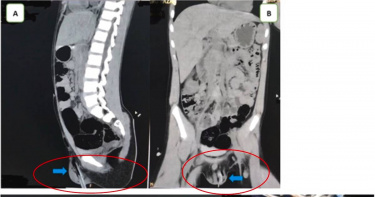

11歲男童「胃脹食不下嚥」暴瘦4kg 醫檢查見「1器官被壓扁」親曝解方

台中一名11歲男孩3個月暴瘦4公斤,食不下嚥,胃脹難忍,不時感覺噁心想吐,父母以為孩子得了厭食症四處求醫,卻被當胃炎醫治,後來輾轉到澄清醫院中港院區兒科就診,醫師廖子涵發現該男孩是罹患「上腸繫膜動脈症候群」,造成十二指腸被壓扁,食物無法通過,該病症須透過「增胖」治療,醫師讓男孩改吃流質的營養食物,同時也開立促進食慾以及止吐藥物,一段時間後病情果然有所改善。廖子涵醫師指出,該名男孩3個月前突然胃口變得不好,且情況越來越差,一吃東西就想吐,後來甚至完全吃不下東西,體重也從30公斤瘦到26公斤,身體質量指數(BMI)僅剩15.05 kg/m2,父母帶著孩子四處求醫,卻被當胃炎醫治,吃藥情況完全沒有好轉。後來男孩輾轉到澄清醫院中港院區兒科就診,經超音波和電腦斷層檢查發現,男孩的主動脈與上腸繫膜動脈之間夾角只有23度,不過正常角度為約38到65度之間,而造成該情況常見原因是體重過輕,導致上腸繫膜動脈缺少脂肪支撐,壓迫到十二指腸,導致食慾不振與頻繁的噁心嘔吐;若為此原因造成可考慮進行「增胖」治療,增加上腸繫膜動脈支撐的脂肪,讓夾角增大減少對十二指腸的壓迫。廖子涵醫師讓男孩改吃流質的營養食物,同時給予促進食慾以及止吐藥物,2個多月後,男孩體重逐漸增加,病情獲得改善。廖子涵指出,醫學統計分析顯示兒童罹患上腸繫膜動脈症候群的機率約為0.05%,若孩子出現不明原因的體重下降,要盡快就醫找出真正的原因。